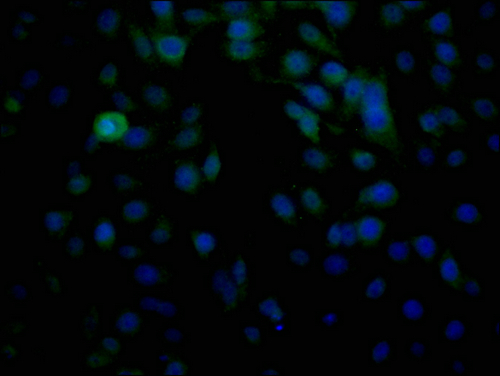

• Immunofluorescence staining of HepG2 cells with CSB-PA361187LA01HU at 1:100, counter-stained with DAPI. The cells were fixed in 4% formaldehyde and blocked in 10% normal Goat Serum. The cells were then incubated with the antibody overnight at 4°C. The secondary antibody was Alexa Fluor 488-congugated AffiniPure Goat Anti-Rabbit IgG(H+L).